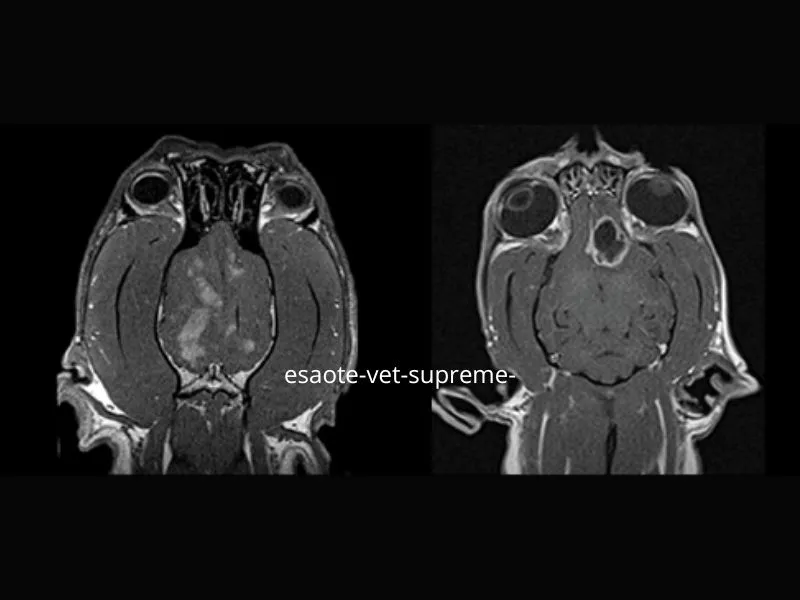

Clinical images

Small animals